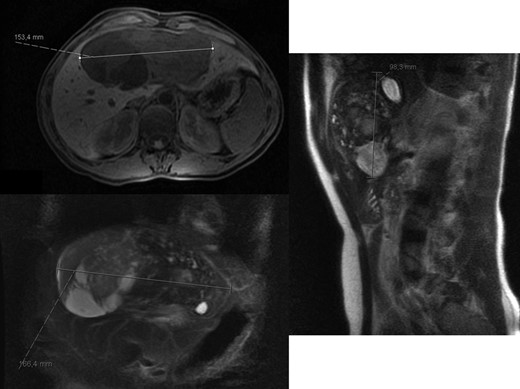

A 40-year-old woman with past medical history of c-section at the age of 26, was referred to our Hepatobiliary Unit in 2013, with diagnose of liver tumor with 16.6 cm (Fig. 2) suggestive of solitary fibrous tumor.

Abdominal Magnetic Resonance – heterogeneous liver mass in segment 4 with 16.6 cm.

No distant metastasis was identified.